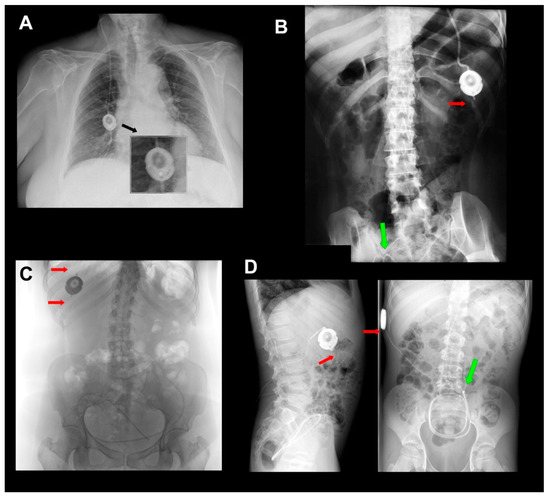

- Due to the risk of fracture in the catheters at the level of the proximal or distal connectors of the valve, it is advisable to include in the patient’s follow-up periodic radiological controls for ruling out this potential problem.